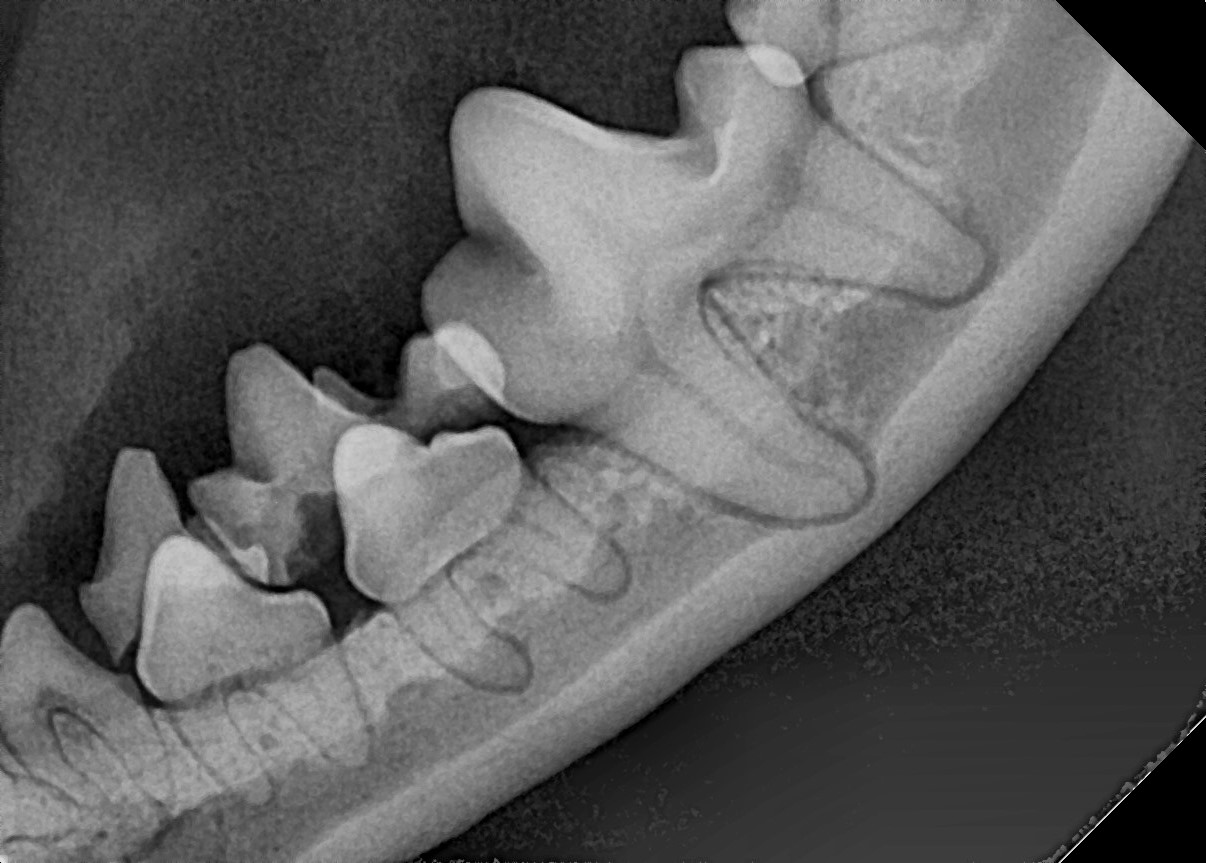

잔존 유치가 탈락되지 않아 영구치가 치아 사이에 같혀 있음 위 사진은 유치가 제때 탈락되지 않아 영구치가 세 번째 앞니 아래에 갇혀 있는 것을 보여줍니다.

세 번째 앞니도 송곳니 간섭으로 인해 정상위치 보다 위쪽으로 벗어나 있는 것(deviation)을 확인할 수 있습니다.